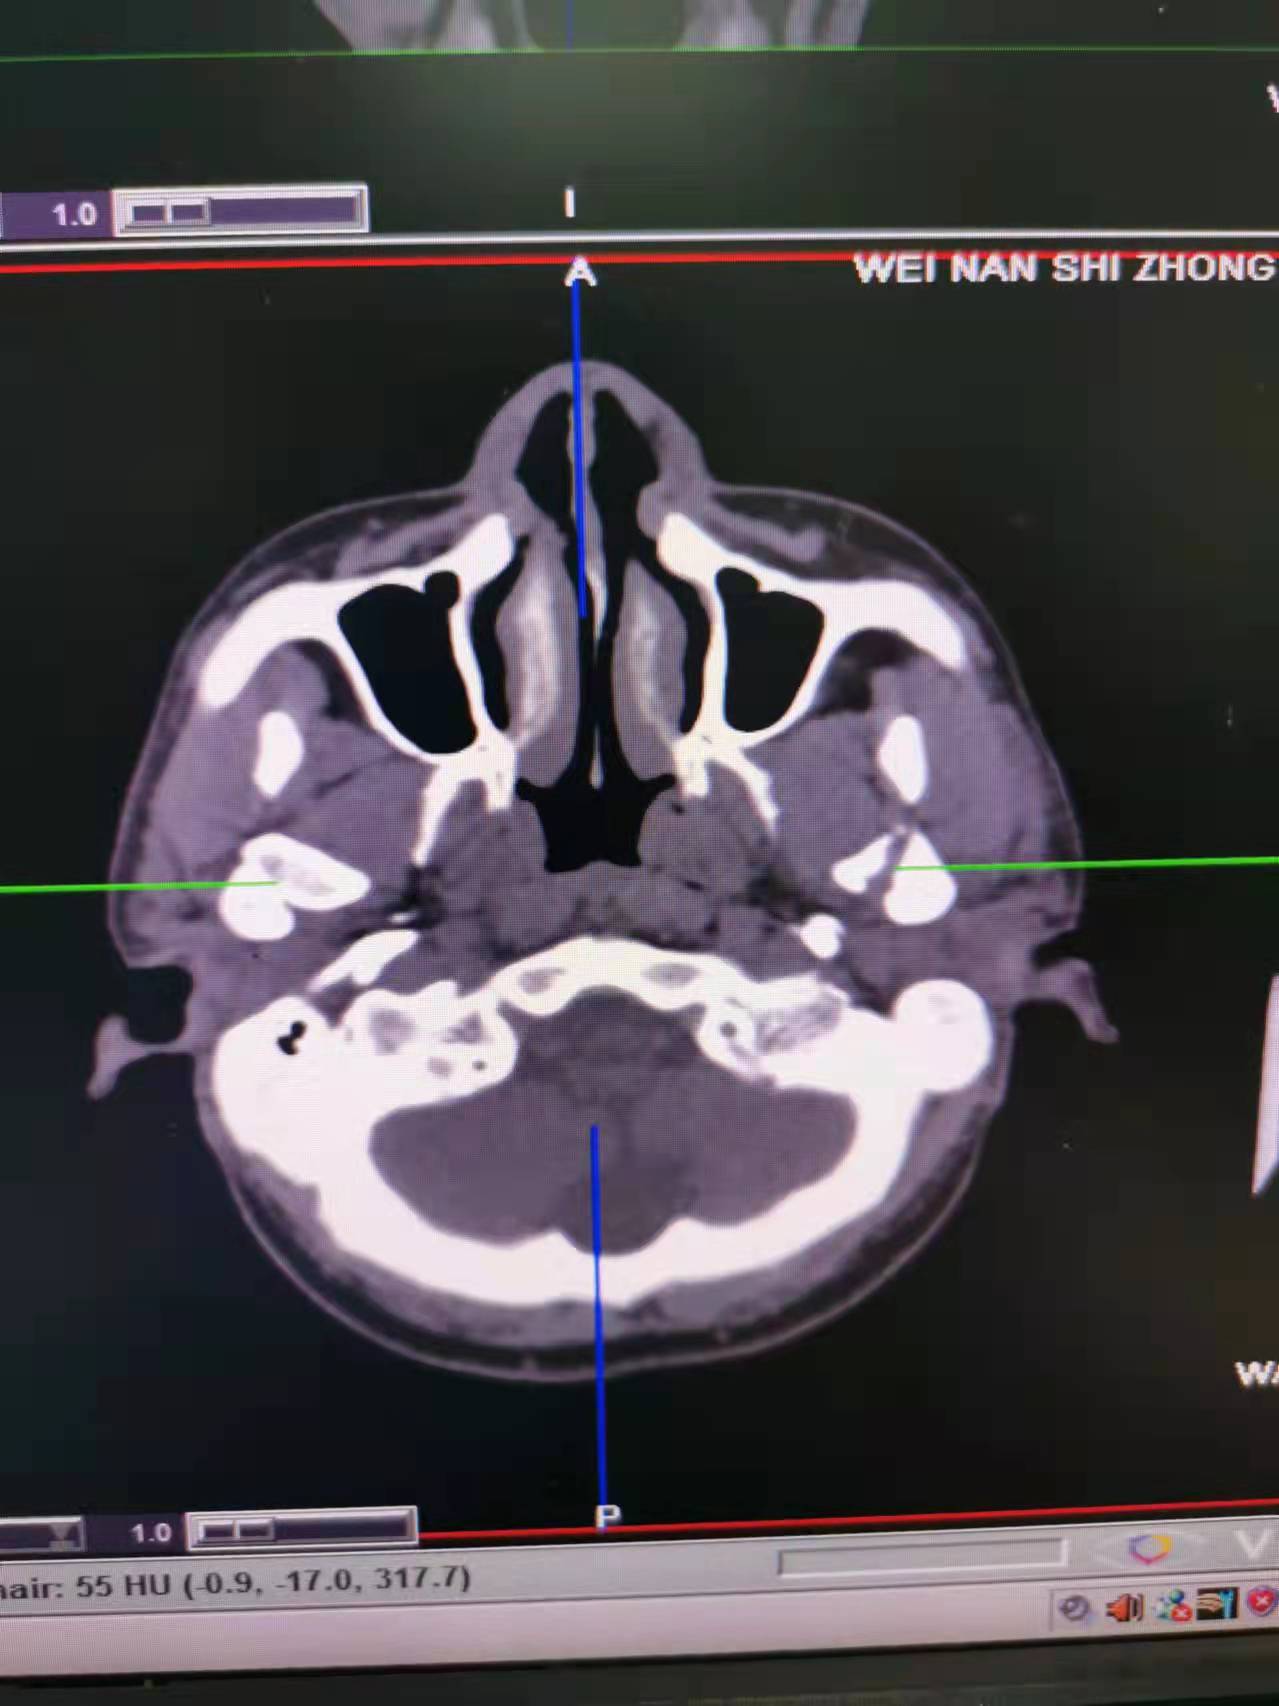

据了解,53岁的患者刘先生在1月25日当天走路不慎摔倒致下颌损伤,造成颏部软组织裂伤和张口困难,前往当地卫生院进行颏部裂伤清创缝合术。术后辗转到乐鱼在线登录入口口腔科门诊就诊,并进行颌面部CT检查提示为下颌颏部正中和双侧髁状突骨折,双侧下颌升支高度不一致,右侧较左侧变短1cm,张口重度困难,咬合关系错乱。刘先生因考虑在春节过后再入院治疗,于2月8日再次前来口腔科以“下颌骨骨折”收治人院。

口腔科主治医师蔺非非为患者入院后进行完善术前常规检查和颌间牵引恢复咬合关系。科主任李瑞春结合患者实际病情和检查结果认为,患者的髁突骨折在下颌骨骨折中所占比例较高,约为17.0%-36.3%。髁突骨折时,耳前区有明显的疼痛,局部肿胀、压痛。通过手指深入外耳道或在髁突部触诊,如张口时髁突运动消失,可能有骨折段移位。双侧低位骨折时,2个髁突均被翼外肌拉向前内方,双侧下颌支被拉向上方,可出现后牙早接触,前牙开秴。髁状突骨折易引起下颌后缩,张口困难,咬合关系错乱,关节强直等并发症。考虑患者系陈旧性骨折应尽早实施手术,避免骨折导致的张口困难、关节强直等并发症。因患者已经错过最佳治疗时期,决定尽快为患者进行手术治疗。

科主任李瑞春和主治医师蔺非非经过缜密的术前讨论和充分评估,手术在全身麻醉下进行,术中克服术野狭小操作不便困难,将下颌骨骨折完好对位,顺利地完成了"双侧髁状突和下颌颏部正中骨折切开复位内固定术"。术后检查患者面部对称,双侧下颌升支高度一致,咬合关系已恢复。